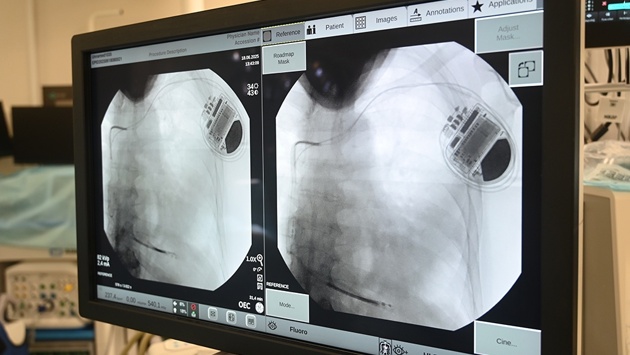

Подкожный кардиовертер-дефибриллятор устанавливается под широчайшую мышцу спины в подмышечной области, а электрод проводится подкожно на переднюю грудную стенку и устанавливается в проекции сердца. Прибор контролирует активность сердца и, когда оно останавливается, начинает биться неправильно, слишком медленно или слишком быстро, благодаря специальным алгоритмам аппарат посылает электрические импульсы, позволяющие восстановить нормальный сердечный ритм.

Впервые подкожную систему кардиовертера-дефибриллятора установили пациенту медики больницы им. В.В. Вересаева год назад. Сегодня такие вмешательства проводят в операционных ГКБ им. С.С. Юдина, ГКБ им. В.В.Вересаева и ГКБ им. И.В. Давыдовского.